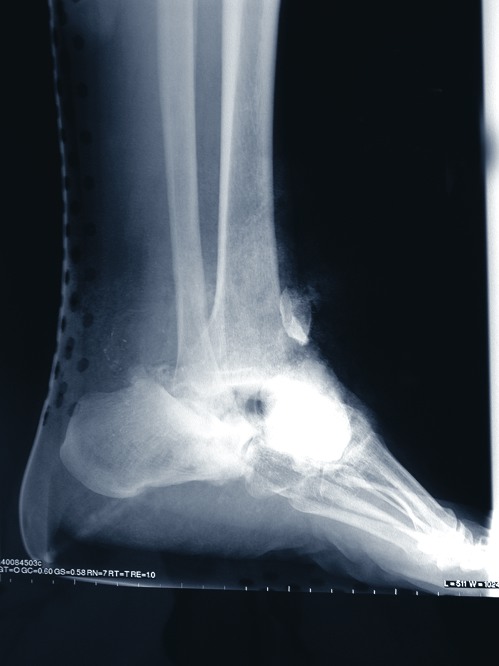

In a follow-up column to the previous discussion of lower extremity traumatic wounds (see “Essential Insights On Managing Traumatic Wounds,” page 32, September issue), the panelists discuss key principles in treating open fracture wounds in the forefoot and toes. They also share their thoughts on the use of plastic surgery techniques and advanced wound closure modalities. Without further delay, here is what the panelists had to say. Q: How do you manage simple open fracture wounds in the forefoot/toes? A: A. Douglas Spitalny, DPM, points out the so-called simpler fractures of the forefoot and toes have had the highest infection rate and long-term sequelae as a group. He has seen many cases of post-injury gangrene. He notes that surgeons often forget to treat nail plate and nail bed injuries as open fractures. Dr. Spitalny adds that open digital and forefoot fractures seem to have a much higher rate of post-traumatic pain. He says stump neuromas, degenerative joint disease, the development of digital contractures, adhesive capsulitis, tendonitis, painful scars, fibromas, nonunions and/or malunions all seem to occur more frequently than reported. “Although we tend not to manage these simpler cases in a formal OR setting, I do think these injuries are often overlooked and are still deserving of a formal wash out even in the ER or clinic,” explains Dr. Spitalny. “The principles of managing these injuries should remain the same regardless of location.” Dr. Spitalny notes he has always worked in a hospital system that accepts open fractures as open injuries regardless of size and location. He is often able to wash out the wound in the ER, provide some temporary relief and discuss the need for a formal surgical debridement in the operating room the same day. Then he will develop a game plan for follow-up debridement and/or consultations. When treating open fractures, Jordan Grossman, DPM, suggests evaluating the mechanism of injury, the circumstances contributing to bacterial contamination, the extent of soft tissue destruction and loss of function. The treatment goals should include preventing infection, restoring function and providing adequate soft tissue coverage, according to Dr. Grossman. He emphasizes prompt operative intervention with copious irrigation and excisional debridement. When it comes to managing minimally displaced open fractures, such as phalangeal fractures and distal tuft fractures, Dr. Grossman says one may use primary closure and immobilization. He says primary closure is only indicated in clean wounds with no extensive tissue loss. While open fractures of the phalanges are not common, Lawrence DiDomenico, DPM, says one will see these fractures more often with crush injuries. He adds that toe fractures are the most common osseous injury to the forefoot. Since great toe fractures differ both functionally and anatomically, Dr. DiDomenico says one must recognize and consider the soft tissue attachments. A fracture of the proximal phalanx of the fifth toe, which is also called “the night walker fracture,” is particularly common, according to Dr. DiDomenico. He says the injury results from direct trauma or stubbing the toe. In the case of obvious radiographic deformity such as rotational malalignment or displacement, Dr. DiDomenico says one should perform reduction under anesthesia with either open or closed techniques based on the extent of the deformity. Post-op care entails a short leg walking cast or a hard-soled shoe for four to six weeks. He points out that malalignment and neglect can lead to painful prominences. When it comes to more extensive comminuted or crush injuries of multiple digits and metatarsals, Dr. Grossman says it is frequently better to pursue temporary stabilization with K-wires or mini-external fixators, which can maintain length in the face of bone loss and severe comminution. Employing temporary fixation should achieve stability and minimize both dissection and further soft tissue insult, according to Dr. Grossman. While it is crucial to manage these wounds aggressively, Dr. Grossman says surgeons should delay definitive internal fixation until they have adequately recovered the soft tissues and the threat of infection is low. In regard to devitalized digits, Dr. Grossman says one may proceed to perform a primary amputation. In some cases, he notes surgeons may reserve the soft tissue envelope for subsequent flap coverage. Dr. Grossman emphasizes that a higher degree of soft tissue injury traditionally carries a worse prognosis for the patient. He says these injuries often lead to amputation as well as prolonged recovery and rehabilitation. In cases of partial thickness skin loss, Dr. Grossman notes one should facilitate healing via secondary intention and grafting. He adds that oral antibiotics may or may not be required, depending on the extent of the injury. Q: When do you utilize plastic surgery/advanced wound closure techniques? What type of techniques do you use? A: Dr. Grossman suggests closing wounds with plastic surgery when faced with inadequate soft tissue coverage over exposed granulating bone, tendon or hardware. Surgeons should perform primary closure when a wound shows no signs of infection, is pink and healthy, and has properties of elasticity to allow for closure, advises Dr. DiDomenico. One should handle tissues gently and reapproximate the closure of deep layers anatomically in order to remove tension from the skin. The recipient site of partial or full thickness skin grafts must have sufficient vascularity to support a good base of granulation tissue, point out Drs. DiDomenico and Grossman. They note that exposed tendon, bone and cartilage lacking a good base of granulation will typically not support a graft. Dr. DiDomenico says one usually employs such grafts to cover burn wounds, ulcerations and a loss of soft tissue. While wounds on the dorsum of the foot overlying a relatively thin subcutaneous layer respond well to grafts, Dr. Grossman cautions that plantar wounds are more subject to shear forces and split thickness grafts are often unable to withstand the forces required by prolonged weightbearing. Dr. DiDomenico suggests using artificial grafts briefly to function as a biological dressing and a barrier. He adds that one can use bioengineered skin graft techniques for more chronic wounds. However, Dr. DiDomenico says such wounds must have a good base of granulation and not exhibit any signs of infection or significant drainage in order for good healing to occur. Although it is not difficult to use local flaps such as rotational flaps, V-Y flaps and multiple Z-plasties, Dr. Grossman says these are limited to covering small defects. He points out that local flaps are contraindicated in acute trauma since their quality is compromised when surrounding tissue damage has occurred. Surgeons should reserve free tissue transfers and local flaps for large deficits with extensive soft tissue loss and exposed bone, according to Dr. Grossman. Even when the surgeon performs free flaps successfully, he says there may be significant long term struggles with shearing, callus formation, prolonged edema, loss of muscle function and the need for bracing and accommodative shoegear. Dr. Grossman says DPMs should consult a plastic surgeon for complicated wound closures and reconstructions. While he notes he is not adept with plastic surgery techniques, Dr. Spitalny will not hesitate to consult a plastic surgeon but does not turn cases over to the plastic surgeon. “Plastic surgeons are excellent consultants but we are far more capable of managing foot and ankle wounds,” emphasizes Dr. Spitalny. “If they know you are capable of managing such wounds, I assure you they will send it your way.” Dr. Spitalny says he will ask for a plastic surgeon’s assistance on a free muscle graft or rotational flap. However, he does not see much value in plastic surgery until wounds are clean and viable and fractures have been stabilized. He adds that rotational flaps, skin expanders or even skin grafts have little place early in treatment. However, Dr. Spitalny emphasizes that the early use of negative pressure wound therapy (VAC, KCI) has “simply revolutionized trauma surgery.” Lawrence Karlock, DPM, concurs about the efficacy of the VAC, saying it promotes granulation tissue over deep exposed tendon and allows for more definitive coverage of soft tissue. Dr. DiDomenico is a Fellow and member of the Board of Directors of the American College of Foot and Ankle Surgeons. He is a Diplomate of the American Board of Podiatric Surgery and an Adjunct Professor at the Ohio College of Podiatric Medicine. He is the Director of the Reconstructive Rearfoot & Ankle Surgical Fellowship at the Ankle and Foot Care Centers at the Ohio College of Podiatric Medicine. Dr. Grossman is Chief of the Section of Podiatry at the Akron Medical Center in Akron, Ohio. He is a Fellow of the American College of Foot and Ankle Surgeons and a Diplomate of the American Board of Podiatric Surgery. Dr. Spitalny is a staff podiatrist at St. Mary’s Duluth Clinic in Duluth, Minn. He is a Fellow of the American College of Foot and Ankle Surgeons and a Diplomate of the American Board of Podiatric Surgery. Dr. Karlock (pictured) is a Fellow of the American College of Foot and Ankle Surgeons, and practices in Austintown, Ohio. He is a member of the Editorial Advisory Board for WOUNDS, a Compendium of Clinical Research and Practice. Editor’s note: For the first part of this discussion, please see the September 2005 issue or check out the archives at www.podiatrytoday.com.